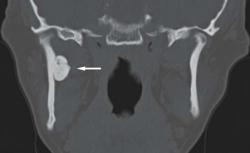

Добавлю еще КТ сканы этого пациента. В данном случае были жалобы на головные боли, КТ подтвердило наличие остеомы с агрессивным ростом. Обратите внимание, "свежая" задняя часть остеомы на КТ имеет меньшую плотность и вид "матового стекла", в отличии от передней порции с выской плотностью компактной кости.

Спасибо за комментарий и за представленный интересный случай, который подтвержден не только рентгенологически, но и КТ. Цит Вас: "Добавлю еще КТ сканы этого пациента. В данном случае были жалобы на головные боли, КТ подтвердило наличие остеомы с агрессивным ростом".

Однако необходимо добавить, что в представленном Вами случае, чисто с точки зрения «классической рентгенологии», образование имеет не только неоднородную структуру, но и полициклический, можно даже сказать «бугристый контур», что безусловно не свидетельствует о её «спокойном состоянии» и уж точно не свидетельствует о «благонадежности». Признаки агрессии налицо, и не только с учетом структуры и контуров, но и имеет место снижение прозрачности лобной пазухи слева – возможно «парапроцесс»? А «тяжик» от контура опухоли, направленный латерально, где чётко дифференцируются очаговые изменения? Признаки злокачественности налицо